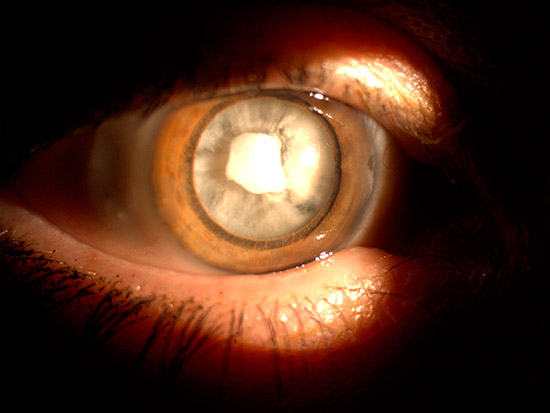

La catarata es cuando la lente interna del ojo, el cristalino, se hace opaco. Provoca disminución de la agudeza visual, visión borrosa, pérdida de intensidad de los colores, deslumbramientos, etc. y estas molestias pueden progresar más o menos rápidamente, según cada paciente.

- Catarata nuclear: Es la más común y suele formarse de forma natural. Se opacifican las fibras del interior del cristalino. Provocan cambios en la refracción hacia la miopía.

- Catarata cortical: Se forman opacificaciones en la corteza del cristalino. Provocan muchos destellos luminosos y crecen más rápido que las nucleares.

- Catarata subcapsular posterior: La opacificación se localiza en la cápsula posterior del cristalino. Son frecuentes en pacientes con tratamiento crónico con corticoides orales. No confundir con opacidad capsular posterior, que es cuando se opacifica la cápsula donde va apoyada la lente intraocular (coloquialmente llamada «lente sucia»). En esos casos se aplica láser y no vuelve a aparecer más.

Exploración del cristalino con lámpara de hendidura: Gracias a la lámpara de hendidura el oftalmólogo puede observar con gran nivel de detalle y aumento la localización y alcance de la catarata.